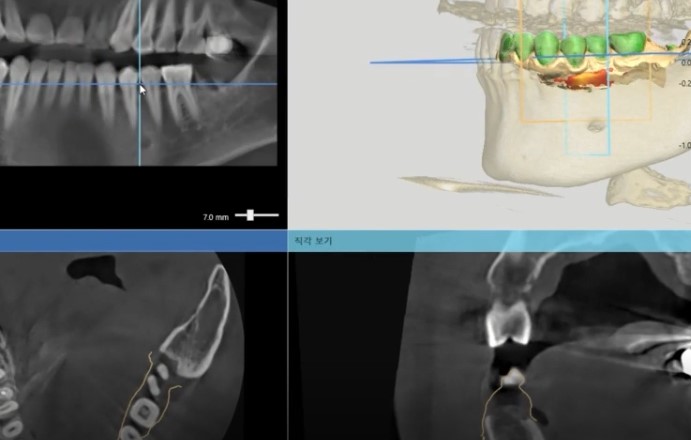

강서구 마곡 치과 에서는

디지털 가이드를 활용하여

잇몸을 크게 절개하지 않고

필요한 위치에만 정밀하게 식립하므로

회복 속도가 빠르고

감염 위험을 낮출 수 있다 설명해 드립니다.